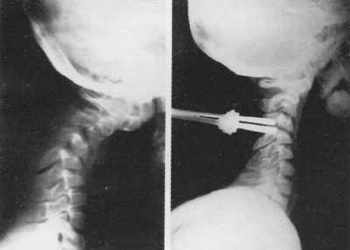

В одном случае у мальчика 9 лет после операции ламинэктомии на уровне С3-С4

в связи с нейрофиброматозом и наличием опухоли в позвоночном канале через 3

мес сформировался грубый кифоз 45°. Ему был наложен галоаппарат, в котором произведена

коррекция кифоза на 35°. Вторым этапом проведена задняя фиксация шейного отдела

по технике Люке. Галоаппарат был снят через 3 мес после операции. Кифотическая

деформация при динамическом наблюдении не нарастает (рис. 4, 5).

| Рис. 4. Постламинэктомический кифоз,

коррекция в галоаппарате. |